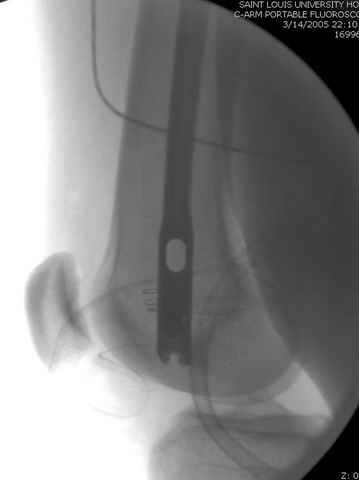

По поводу открытого перелома больной ургентно взят на ретроградное интрамедулярное штифтование, после рутинного дебрайдмента и фасциотомии на бедре и на голени.

интраоперационные